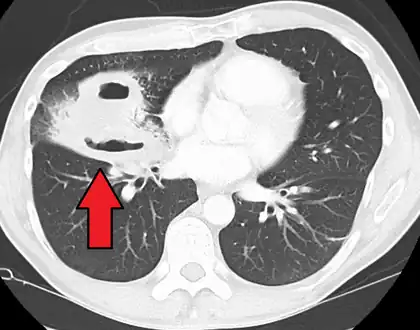

| CT scan showing bilateral pneumonia with abscesses and effusions. | |

Lung abscesses are often on one side and single involving posterior segments of the upper lobes and the apical segments of the lower lobes as these areas are gravity dependent when lying down. Presence of air-fluid levels implies rupture into the bronchial tree or rarely growth of gas forming organism.

Pulmonary abscess on CT scan -